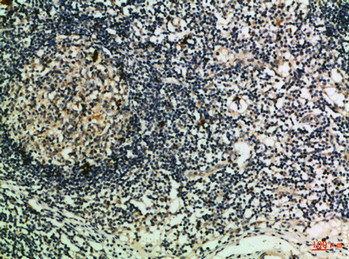

IHC (Immunohistochemisry)

(Immunohistochemical analysis of paraffin-embedded Human-lymph, antibody was diluted at 1:100)